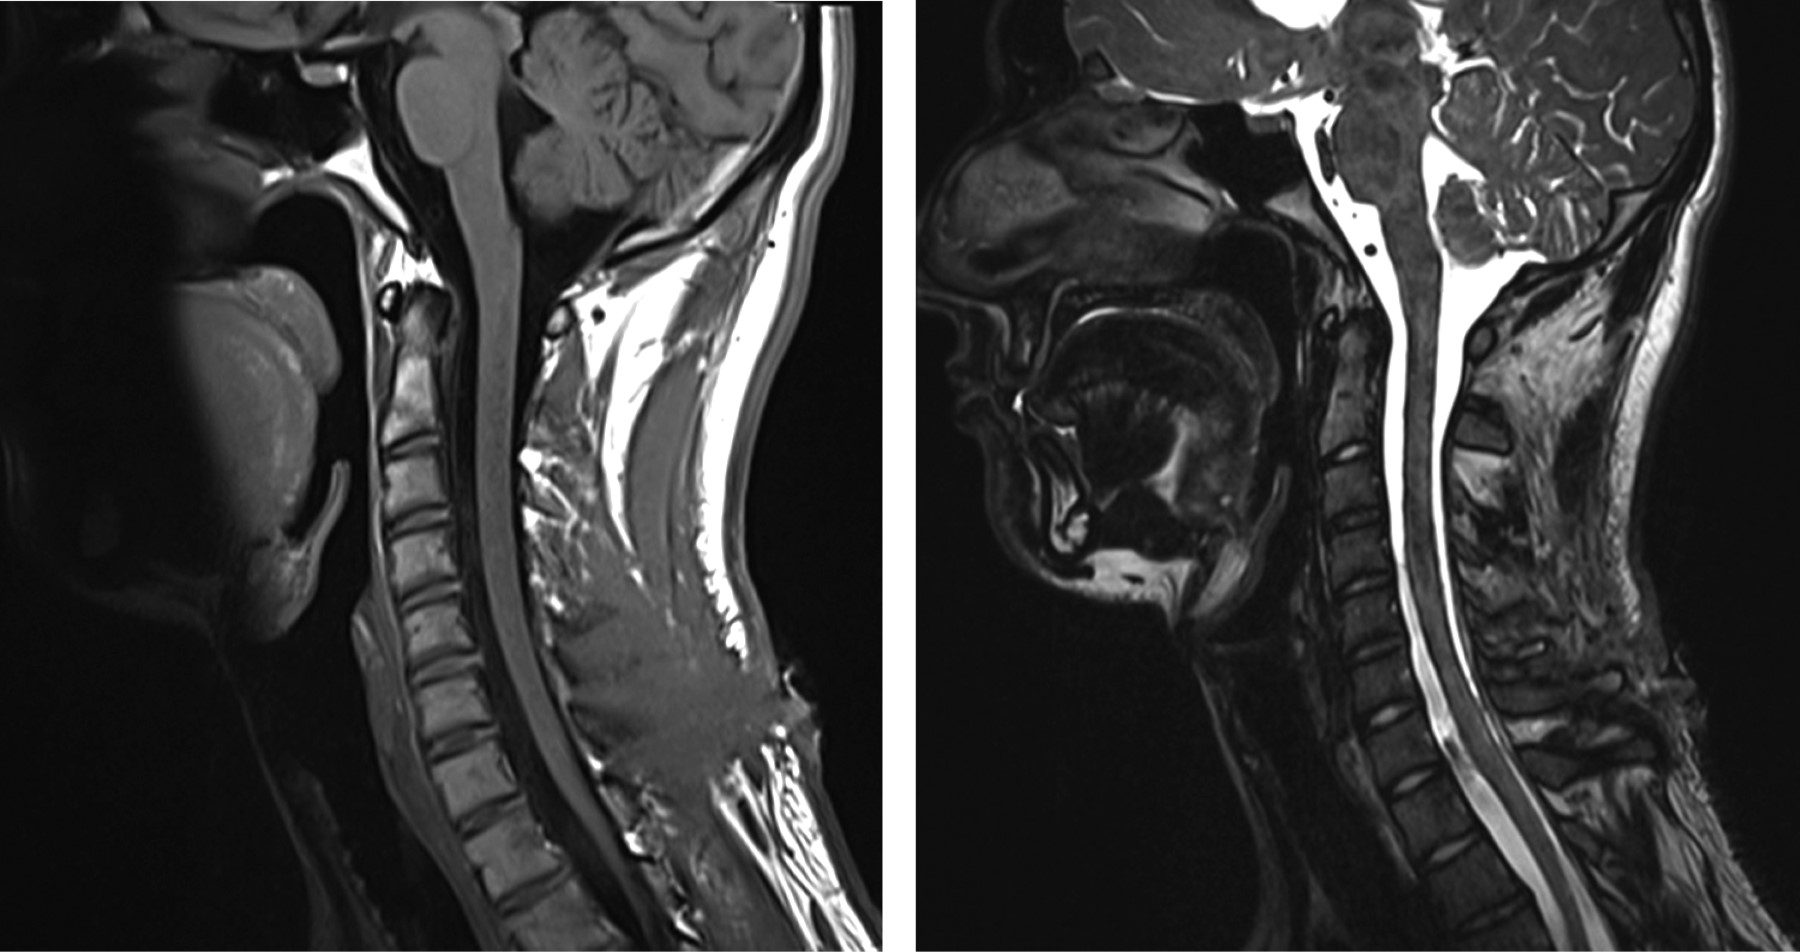

Introduction: spinal subdural hemorrhage is rare and potentially devastating. It occurs most frequently in lumbar puncture, spinal anesthesia, therapeutic anticoagulation and coagulation disorders, and spinal tumors or vascular malformations. Case presentation: we describe a case of a 17-year-old man with intracranial and cervicothoracic hemorrhage secondary to acute trauma with neurological deficit in whom surgical treatment had a good outcome. Conclusions: It has been shown that surgical intervention, as in all acute spinal cord compression, surgical treatment must be rapid above all and is associated with neurological deterioration (motor or sensory). An expectant management is possible if early neurological recovery occurs in the context of a good neurological examination on admission with MRI follow-up.

Figure 2